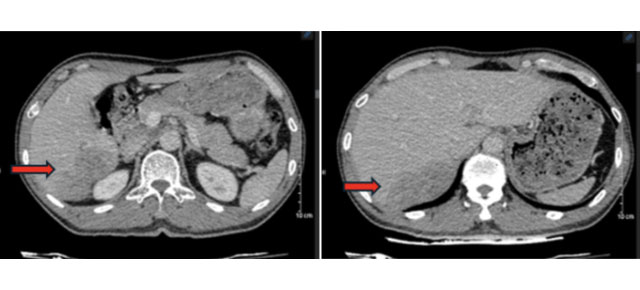

Sau khi chụp chiếu, bác sĩ chẩn đoán bệnh nhân bị ung thư biểu mô tế bào gan, kèm xơ, viêm gan. Bệnh nhân được điều trị bằng liệu pháp toàn thân, thuốc miễn dịch và thuốc đích, kết hợp điều trị viêm gan B.

Sau ba tháng, kích thước khối u gan giảm. Bác sĩ chỉ định phẫu thuật cắt gan phân thùy sau chứa u. Người bệnh tiếp tục duy trì thuốc và nâng cao chất lượng cuộc sống.